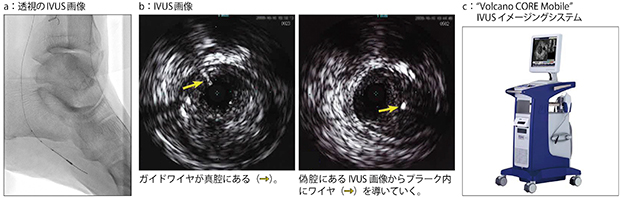

IVUS関連画像例:IVUS併用下肢インターベンションの画像例

このような中,心臓血管センターでは,末梢血管の慢性完全塞栓病変(CTO)におけるインターベンションで,IVUSを積極的に使用している。CTOでは,IVUSの画像を参照することで,ワイヤが血管外に出てしまうリスクを低減できるので全例で用いており,全体でも30~40%の症例でIVUSを使っている(IVUS関連画像例を参照)。使用している装置・治療デバイスは,ボルケーノ・ジャパンのイメージングシステムとIVUSカテーテルの「Eagle Eye」などである。中村所長は,ボルケーノ・ジャパンのIVUS製品について,「フェーズドアレイ方式のIVUSカテーテルは,パッケージから開封してすぐに使用できる簡便性が非常に良いと思います。カテーテル自体も堅牢で,破損などのトラブルがなく,安心して使える信頼性の高さも評価しています」と述べている。実際のインターベンションでは,AlluraClarityファミリーのモニタにIVUS画像を表示して参照しながら手技を進めている。中村所長は,末梢血管のインターベンションにおけるIVUSの有用性について次のように説明する。

「血管の診断・治療は,血管撮影装置の進歩とともに進んできましたが,造影画像や透視画像は,血管の『影』を見ているだけで,正確な血管径を把握できません。症例数の多い冠動脈のインターベンショニストは,手技の経験を積むことで,血管径を把握できるようになります。しかし,まだ症例数の少ない末梢血管のインターベンションでは,IVUSを用いることで血管径や病変の長さを正確に実測し,血管撮影装置の画像に情報を追加することになるので,治療の精度を高められます。特に,CTO症例では,透視画像を見ながらカテーテルを操作しますが,実際に血管の真腔を通っているのか判断できない場合があります。それがIVUSを使うことで,カテーテルの正確な位置を知ることができ,治療成績の向上にもつながっています」